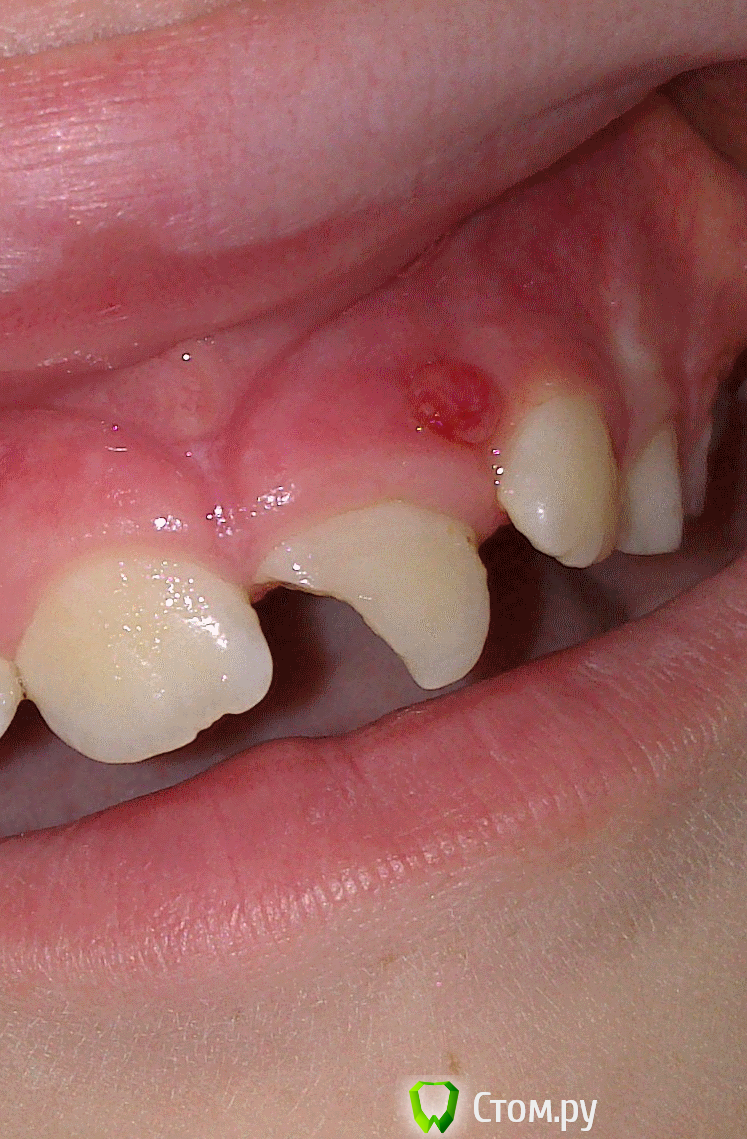

Kykysyavika Опубликовано 27 января, 2014 Поделиться Опубликовано 27 января, 2014 (изменено) В середине декабря 2013 обратился пациент 12 лет с жалобами на боли при накусывании в области центральных резцов верхней челюсти, припухлость верхней губы. Из анамнеза: более двух лет назад была травма зуба 21, скол медиального угла коронковой части. Лечение не проводилось. Жалоб не было, но, как выяснилось, зубом этим "не пользовался". пищу откусывал только правой стороной.На снимке: разрежение костной ткани диаметром 7-8 мл. Полость зуба вскрыла, экссудат прозрачный, немного желтоватый, отмыла гипохлор, ХГ, оставила пульпосептин. Отправила на разрез. Хирург назначил а/б терапию, НПВП, антигистамин.За две недели несколько раз мыла, оставляла пульпосептин- все отлично. Экссудата не было, жалоб не было.На прошлой неделе запломбировала Метапастой. Результат- обострение. Не стоило за этот зуб вообще браться? Изменено 27 января, 2014 пользователем Kykysyavika Ссылка на комментарий

Kykysyavika Опубликовано 27 января, 2014 Автор Поделиться Опубликовано 27 января, 2014 АБ были месяц назад, амоксиклав. И действительно всё было спокойно, до Метапасты. Скорее всего вывела за апекс,да еще гуттой придавила...Сейчас у пациента свищ, (или не свищ???) зуб оставила открытым, (полетели тухлые помидоры)) .Там гной с прожилками крови. Завтра попробую снова закрыть с пульпосептином.Ошибка в выводе кальция за верхушку? Ссылка на комментарий

ромашечка Опубликовано 27 января, 2014 Поделиться Опубликовано 27 января, 2014 Судя по фото,разрезу- самое время. Я так поняла, это фото -после обострения после матапасты? А разрез был -до. А то , что на фото -как по мне -"зреет свищ"- и вот-вот вскроется, достаточно зондом "ковырнуть" и польёт, согласна с anvladd. Может ошибаюсь. Ссылка на комментарий

Kykysyavika Опубликовано 28 января, 2014 Автор Поделиться Опубликовано 28 января, 2014 Открытым не оставлять никогда!!! Отмывать долго затем кальций или метапекс и тд. Зачем гутта с метапастой?Я иногда придавливаю пальцем вестибулярно аккуратно, через канал аж брыжжет.Разрез лишний.У меня,к сожалению,не было достаточно времени для полноценной обработки, поэтому оставила открытым. И, если честно, я не ярый противник этого старинного метода. Кальций гуттой я "утромбовала". Разрез был больше месяца назад, а на фото - после Метапасты обострение Ссылка на комментарий